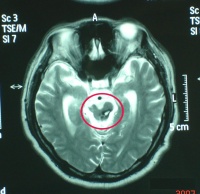

脑干损伤CT图

脑干损伤与继发性脑干损伤的区别在于症状,体征出现的早晚。继发性脑干损伤的症状、体征皆在伤后逐渐产生。颅内压持续监护亦可鉴别:原发性颅内压不高,而继发性则明显升高。同时,CT和MRI也是鉴别诊断的有效手段。在显示脑实质内小出血灶或挫裂伤方面,尤其是对胼胝体和脑干的细微损害,MRI明显优于CT。脑干听觉诱发电位可以较准确地反映脑干损伤的平面及程度。通常在听觉通路病灶以下的各波正常,病灶水平及其上的各波则显示异常或消失,颅内压监护连续测压亦有鉴别原发性或继发性脑干损伤的作用,虽然二者临床表现相同,但原发者颅内压正常,而继发者明显升高。